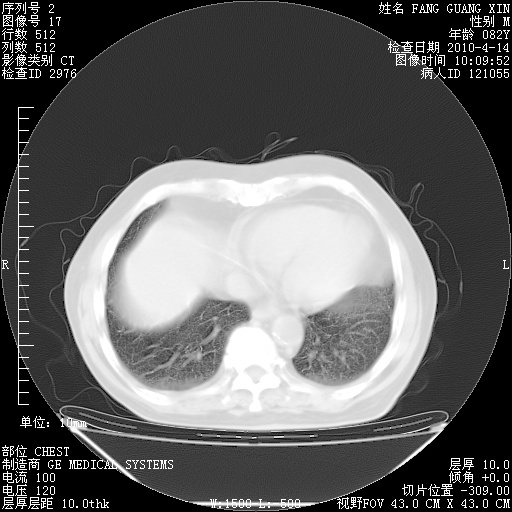

4月14日肺部CT

4月28日肺部CT——再次出现类似去年5月9日——透光度降低,(影像科认为)“间质性”改变。

4月28日肺部CT——再次出现类似去年5月9日——透光度降低,“间质性”改变。